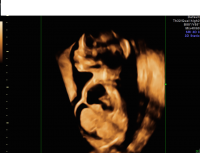

Hydrops 3D

Hydrops pleural effusions and ascites view

If suspected, a detailed ultrasound will be performed to look for other abnormalities. Fetal echocardiography will be recommended to further evaluate fetal heart structure and function. As infections, other anomalies, and genetic abnormalities are commonly associated with this finding, genetic counseling and diagnostic testing are recommended. In cases where severe anemia is suspected as a cause, cordocentesis may be recommended. Prenatal care will be managed by a maternal-fetal medicine specialist, an obstetrician with special training and expertise in high-risk pregnancies. The pregnancy will be closely monitored, as will the mother who is at risk for specific health complications. Prenatal consultations with neonatology and other pediatric subspecialists may be recommended to discuss the condition, its prognosis, and management after birth.